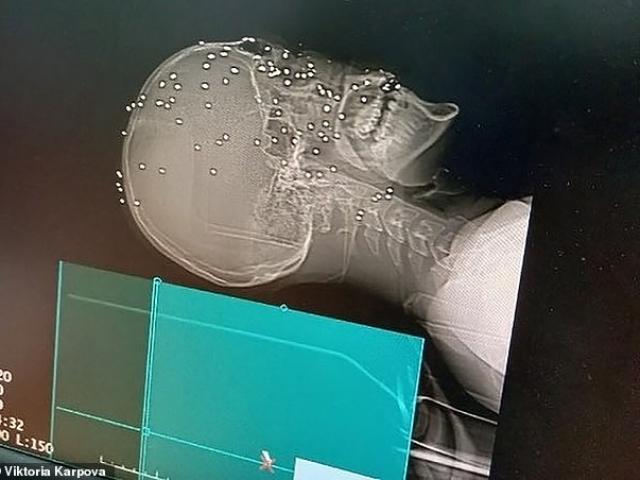

Khuôn mặt của người đàn ông bị biến dạng sau khi bị thú dữ tấn công.

Ông Pedro Vaz Ferreira bị thương nặng ở mặt sau khi bị con báo đốm tấn công. Ảnh: New Flash

Davi chia sẻ với tờ O Liberal: "Tôi cùng bố và em trai đi săn trong rừng thì đột nhiên con báo đốm lao tới, chỉ nhắm vào bố tôi. Con báo khiến mặt của bố tôi biến dạng, mũi bị gãy và một bên mắt bị mù. Móng vuốt sắc nhọn của con báo đốm chọc thẳng vào mắt ông ấy".

Ông Pedro được chuyển ngay tới Bệnh viện Wilson da Mota Silveira trong tình trạng bị thương nghiêm trọng. Hôm 8/11, người nông dân 67 tuổi được chuyển tới một bệnh viện lớn hơn, cách bệnh viện cũ 200 km. Tình trạng của ông Pedro đã khá hơn rất nhiều.